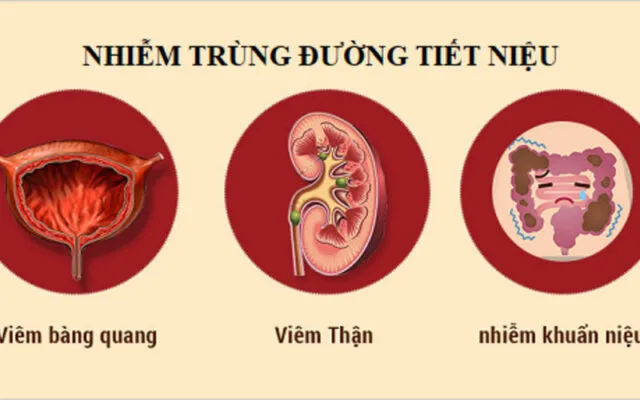

5 dấu hiệu viêm đường tiết niệu

Cảm giác nóng rát, khó chịu khi đi tiểu, tiểu nhiều lần nhưng lượng ít…...

Nhiễm trùng đường tiết niệu là gì?

Nhiễm trùng đường tiết niệu (UTI) là một vấn đề sức khỏe phổ biến, ảnh...

Viêm đường tiết niệu nữ

Bạn có thường xuyên cảm thấy khó chịu khi đi tiểu? Đau bụng dưới và...